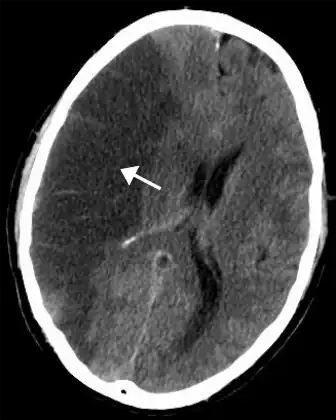

| CT scan of the brain showing a prior right-sided ischemic stroke from blockage of an artery. Changes on a CT may not be visible early on.[1] | |

The biggest risk factor for stroke is high blood pressure.[7] Other risk factors include high blood cholesterol, tobacco smoking, obesity, diabetes mellitus, a previous TIA, end-stage kidney disease, and atrial fibrillation.[2][7][8] Ischemic stroke is typically caused by blockage of a blood vessel, though there are also less common causes.[13][14][15] Hemorrhagic stroke is caused by either bleeding directly into the brain or into the space between the brain's membranes.[13][16] Bleeding may occur due to a ruptured brain aneurysm.[13] Diagnosis is typically based on a physical exam and supported by medical imaging such as a CT scan or MRI scan.[9] A CT scan can rule out bleeding, but may not necessarily rule out ischemia, which early on typically does not show up on a CT scan.[10] Other tests such as an electrocardiogram (ECG) and blood tests are done to determine risk factors and rule out other possible causes.[9] Low blood sugar may cause similar symptoms.[9]